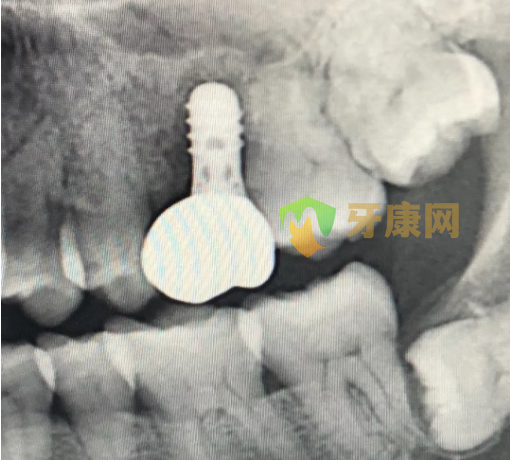

X線片示種植體周低密度影。予以拔除26牙區種植體后搔刮創面,擬擇期再行種植修復。

圖1 種植修復后2月X線片,可見種植體周低密度影